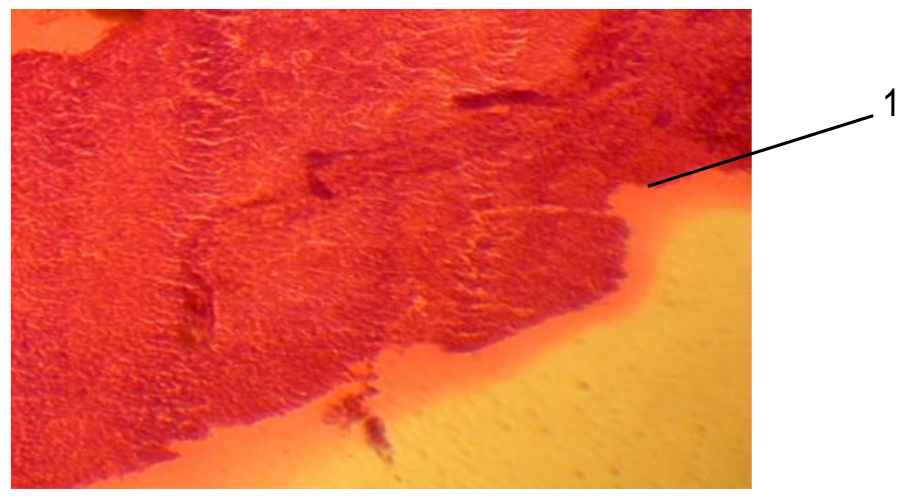

Результаты исследований. Тимус как центральный орган иммунной системы формируется с 30-суточного возраста плода свиней (рис. 1). Масса вилочковой железы в этот период составляет 30,30±0,24 мг‚ длина – 1,20±0,04 см‚ ширина – 0,3±0,01 см. В 90-суточном возрасте плода показатели увеличиваются до 120±2,35 мг, 4,30±0,12 см и 0,60±0,02 см соответственно. В 100-суточном возрасте масса плода и длина вилочковой железы достоверно увеличиваются в 4,5 раза, ширина – в 2 раза, относительно данных плодов свиней 50-суточного возраста.

Рис. 1. Плод свиньи 30-ти суток (гемоксилин-эозин, окуляр 10, объектив 10): 1 – формирующаяся вилочковая железа

Паренхима представлена мезенхимными, эпителиоидными, ретикулярными клетками и лимфоцитами. У 50-суточных плодов дольки тимуса дифференцируются на корковое и мозговое вещество. В корковом веществе долек тимуса количество гемоцитобластов (число клеток в 1 поле зрения) находится на уровне 3,18±0,2, больших лимфоцитов – 3,12±0,1, средних лимфоцитов – 64,48±1,4, малых лимфоцитов – 140,34±4,6. В 90-суточном возрасте плодов количество гемоцитобластов уменьшается на 16%, число больших лимфоцитов увеличивается в 5 раз, средних и малых лимфоцитов – в 2 раза, относительно данных 50-суточного возраста плодов свиней.